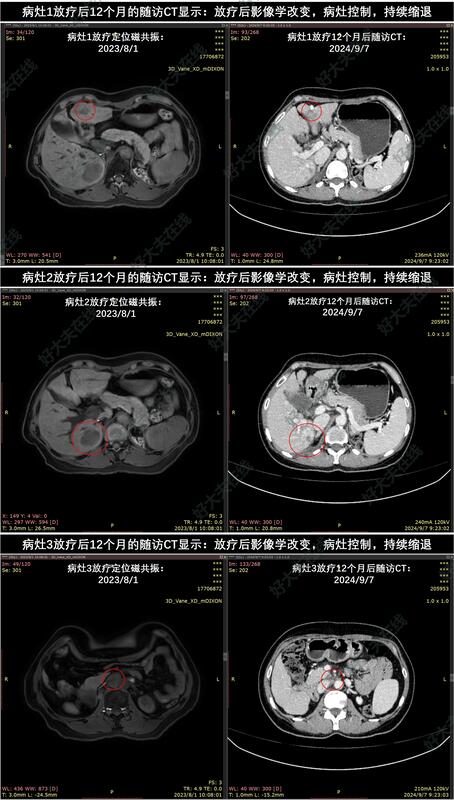

患者于2023年8月完成SBRT放疗:50Gy/8Fx(处方BED=81.3Gy,3个PTV内平均BED依次为112.6Gy,107.5Gy,96.4Gy)。

放疗后18个月的随访CT显示:放疗后影像学改变,3个病灶都持续受控。患者肝功能正常,目前生活质量良好。